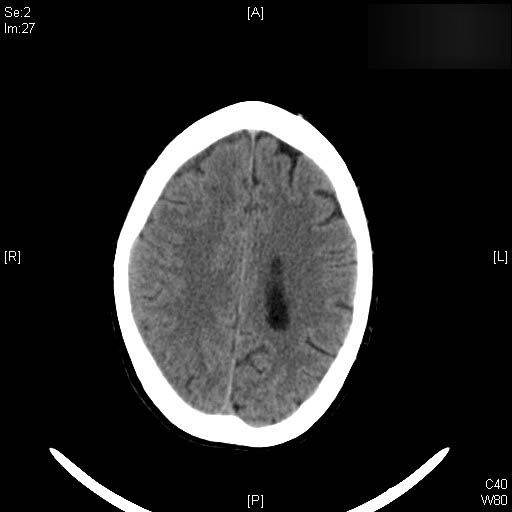

AVC amplio de territorio de A. cerebral media

Hematoma subdural por caída.